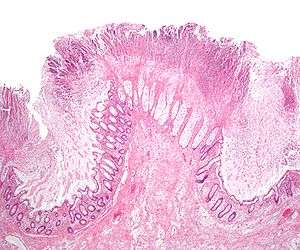

| Pathological specimen showing pseudomembranous colitis | |

The use of systemic antibiotics, including (but not limited to) any penicillin-based antibiotic such as ampicillin, cephalosporins, and clindamycin, causes the normal bacterial flora of the bowel to be altered. In particular, when the antibiotic kills off other competing bacteria in the intestine, any bacteria remaining will have less competition for space and nutrients. The net effect is to permit more extensive growth than normal of certain bacteria. Clostridium difficile is one such type of bacterium. In addition to proliferating in the bowel, C. difficile also produces toxins. Without either toxin A or toxin B, C. difficile may colonize the gut, but is unlikely to cause pseudomembranous colitis.[24] The colitis associated with severe infection is part of an inflammatory reaction, with the "pseudomembrane" formed by a viscous collection of inflammatory cells, fibrin, and necrotic cells.[11]

Prior to the advent of tests to detect C. difficile toxins, the diagnosis most often was made by colonoscopy or sigmoidoscopy. The appearance of "pseudomembranes" on the mucosa of the colon or rectum is highly suggestive, but not diagnostic of the condition.[25] The pseudomembranes are composed of an exudate made of inflammatory debris, white blood cells. Although colonoscopy and sigmoidoscopy are still employed, now stool testing for the presence of C. difficile toxins is frequently the first-line diagnostic approach. Usually, only two toxins are tested for—toxin A and toxin B—but the organism produces several others. This test is not 100% accurate, with a considerable false-negative rate even with repeat testing.

Pseudomembranous colitis first was described as a complication of C. difficile infection in 1978,[70] when a toxin was isolated from patients suffering from pseudomembranous colitis and Koch's postulates were met.